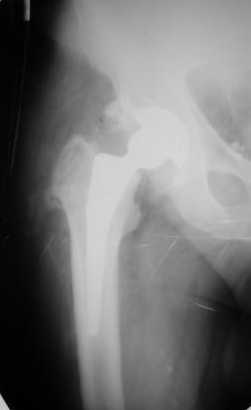

Больной Т. 56 лет, Диагноз: двухсторонний коксартроз 3-4 ст справа, 1-2 ст слева 2.10.08 выполнена операция тотальное бесцементное эндопротезирование. Использовался наружный доступ, положение на боку. Операция протекала без особенностей.

Выполнен послеоперационный ренгеноконтроль в прямой проекции. Рана зажила.

Больное выписан. Рекомендована ходьба без нагрузки 6 нед, рентгеноконтроль через 2 мес. Явка на консультацию На консультации через 7 недель- Больной ходит с дозированной нагрузкой, умеренные боли по задней поверхности правого бедра. Планируется ревизия. Удаление ножки. Установка такой же ножки Corail.

Приходилось ли кому встречаться с такой ситуацией?Вопросы: вросла ли ножка? Какие могут возникнуть сложности с удалением ножки? Нужна ли будет дополнительная трепанация диафиза? И как? Правильный выбор ножка Corail для ревизии в такой ситуации?

Уважаемый Глеб, предложенные снимки впечатлили! Никто не застрахован...